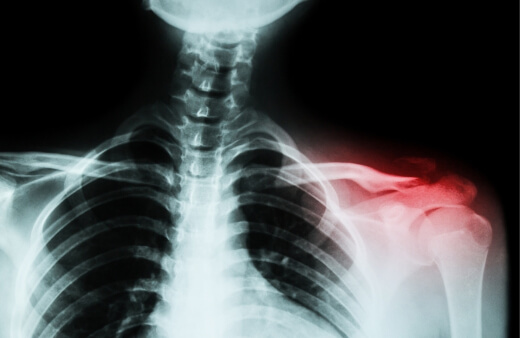

3. Clavicle Fracture

The clavicle is also known as the collarbone. The fracture often happens during a fall.

How Serious are Clavicle Fractures?

A clavicle fracture is a broken bone. It is usually able to heal without any complications. However, in rare instances, the broken bone can damage blood vessels and nerves. The fractures are often treated with surgery and physical therapy. A player can often return to playing after 3 months.

How to Prevent Clavicle Fractures

Clavicle fractures are hard to prevent. But there are some things you can do to strengthen your bones and your body to prevent a clavicle fracture.

- Nutrition for injury prevention

- Wear protective gear

- Incorporate strength training into your regular routine

- Improve flexibility